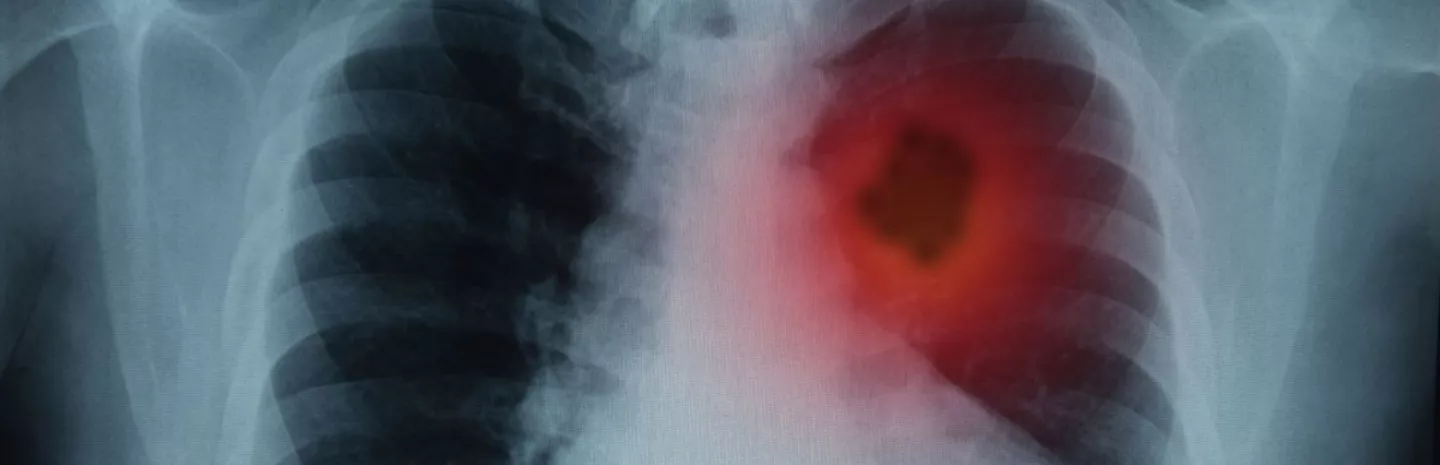

Cancer

Cancer is the #1 killer of Americans aged 45 to 84. Smoking accounts for 30 percent of those deaths. Excess weight, inactivity, poor diet, and alcohol account for another 16 percent. Here’s how to cut your risk.